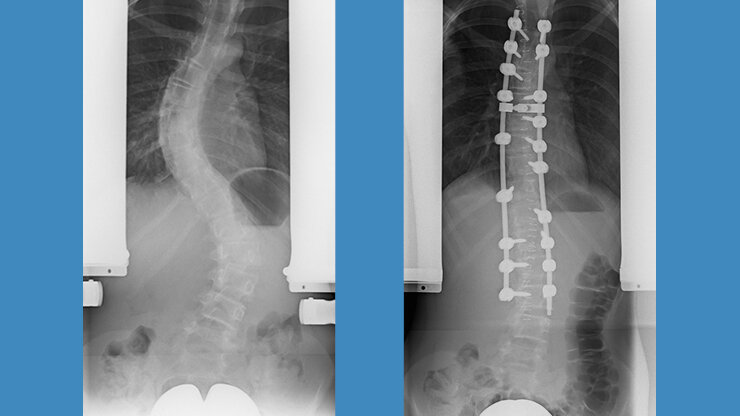

Ventrale Skoliose-Operation

Bei der Operation von ventral, also von vorne, wird entweder durch den Brustkorb oder den Bauch mit seitlichen Zugängen der vordere Anteil der Wirbelsäule erreicht. Diese Methode war bis vor einigen Jahren sehr populär, weil besonders kurzstreckig operiert werden konnte. Sie eignet sich jedoch nur für einbogige Krümmungen der Brust- oder Lendenwirbelsäule und hat den Nachteil, dass der Brustkorb geöffnet werden muss, wovon man sich einige Zeit erholen muss.

16 jähriger Junge mit primär thorakaler Krümmung